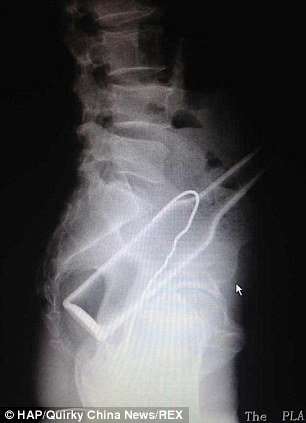

Բժիշկները, ռենտգեն հետազոտություն են արել և ցնցվել են՝ լուսանկարներում տղամարդու աղիքներում շիշ և մետաղալար հայտնաբերելով:

Այդ ժամանակ տղամարդը խոստովանել է, որ շիշը ինքնուրույն է տեղադրել հետանցքի մեջ, սակայն հետագայում չի կարողացել այն դուրս բերել: Սարսափահար եղած նա հիշել է ձկնորսական հմտությունների մասին և փորձել մետաղալարով դուրս հանել շիշը:

Նրա գործողությունների արդյունքում աղքիներում շշի հետ միասին հայտնվել է նաև մետաղալարը: Վիրաբույժների ջանքերի շնորհիվ առարկաները տղամարդու մարմնից դուրս են բերվել: Սակայն դրանով խնդիրները չեն ավարտվել, քանի որ շիշն ու մետաղալարը վնասել են նրա աղիքները, և այժմ նա պետք է բուժման երկարատև կուրս անցնի: